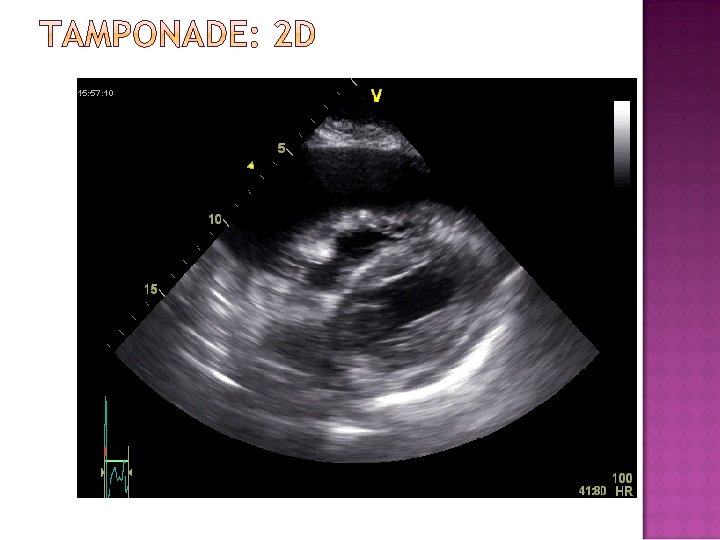

�Pressure in pericardium exceeds s �Compressive effect in intrachamber �Diagnostic techniques � 2 D looking for RA/RV collapse during diastole �M-mode for RA/RV collapse during diastole �Doppler of Mitral and Tricuspid inflow Mitral inflow to decrease by 25% with inspiration Tricuspid inflow increased by 40% with inspiration �IVC diameter fails to increase with inspiration

� Tamponade � Other is a Clinical Diagnosis Detection Methods �EKG �CXR �TTE �R Heart Cath �CT, MRI